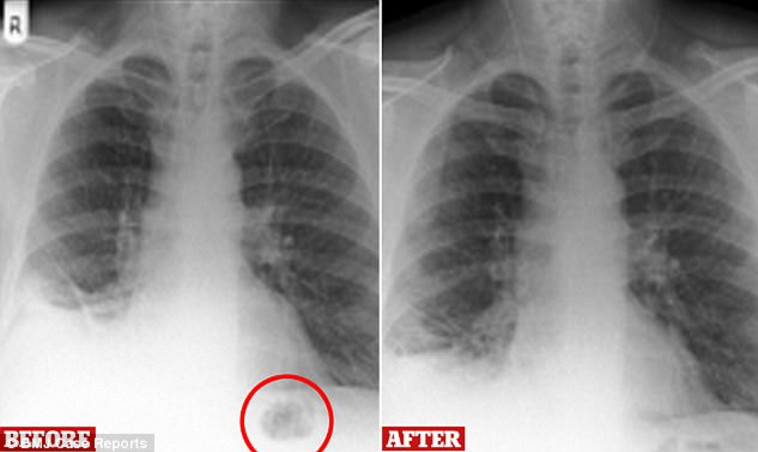

אותו אדם, בן 47, מפרסטון, בריטניה, עישן משך רוב חייו, אך במשך השנה האחרונה השיעול והכיח, שמאפיינים מעשנים כבדים, הלך והחמיר. לאחר שצילומי רנטגן הראו צל קטן על אחת מריאותיו, ולאור היסטוריית העישון שלו, הניחו הרופאים שמדובר בגוש סרטני ושלחו אותו לבדיקות נוספות. אותו גבר הופנה לבית החולים רויאל פרסטון לבדיקת ברונוסקופיה - הליך רפואי בו מוחדר דרך האף או הפה מכשיר עם מצלמה, שבוחן את דרכי הנשימה.

בזכות ההליך הפולשני, התוצאות שלו היו משמחות, והתברר שה"גוש הסרטני" היה קונוס תנועה של פליימוביל, אותו בלע בילדותו. לדבריו של הגבר, הוא אכן קיבל סט פליימוביל בגיל שבע ולא פעם בלע או שאף בטעות חלקים ממנו. המקרה הרפואי, עליו נכתב ב- BMJ Case Reports, הוגדר בידי הרופאים כ"יחיד במינו". הרופאים נדהמו שהצעצוע נשאר במקום כל השנים האלו בלי שהתגלה בבדיקות קודמות.

הרופאים גילו גוש באחת מריאותיו וחששו שיש לו סרטן. צילום מסך

הרופאים גילו גוש באחת מריאותיו וחששו שיש לו סרטן. צילום מסך | הרופאים גילו גוש באחת מריאותיו וחששו שיש לו סרטן. צילום מסך

לדעת הרופאים, זה נדיר שגוף זר לא התגלה במשך 40 שנים. לרוב, כאשר ילד בולע צעצוע מגלים זאת מיד, שכן הם מראי סימני חנק ושיעול. ההשערה שלהם, אותה פרטו בכתב העת, היא שבשל הגיל הצעיר בו בלע הגבר את הצעצוע, הריאות שלו הסתגלו והתפתחו סביבו. "הוא סוף סוף מצא את הפליימוביל האובד שלו, במקום האחרון בו חשב לחפש", נכתב בכתב העת. מעבר לשמחה על כך שלא מדובר בסרטן, לגבר גם הוקל שכן התסמינים שלו הלכו ופחתו, וניכר שיפור משמעותי במצבו ארבעה חודשים לאחר הסרת הצעצוע מגופו.  אם כי לא סביר שהם ייעלמו לחלוטין, בגלל העישון.